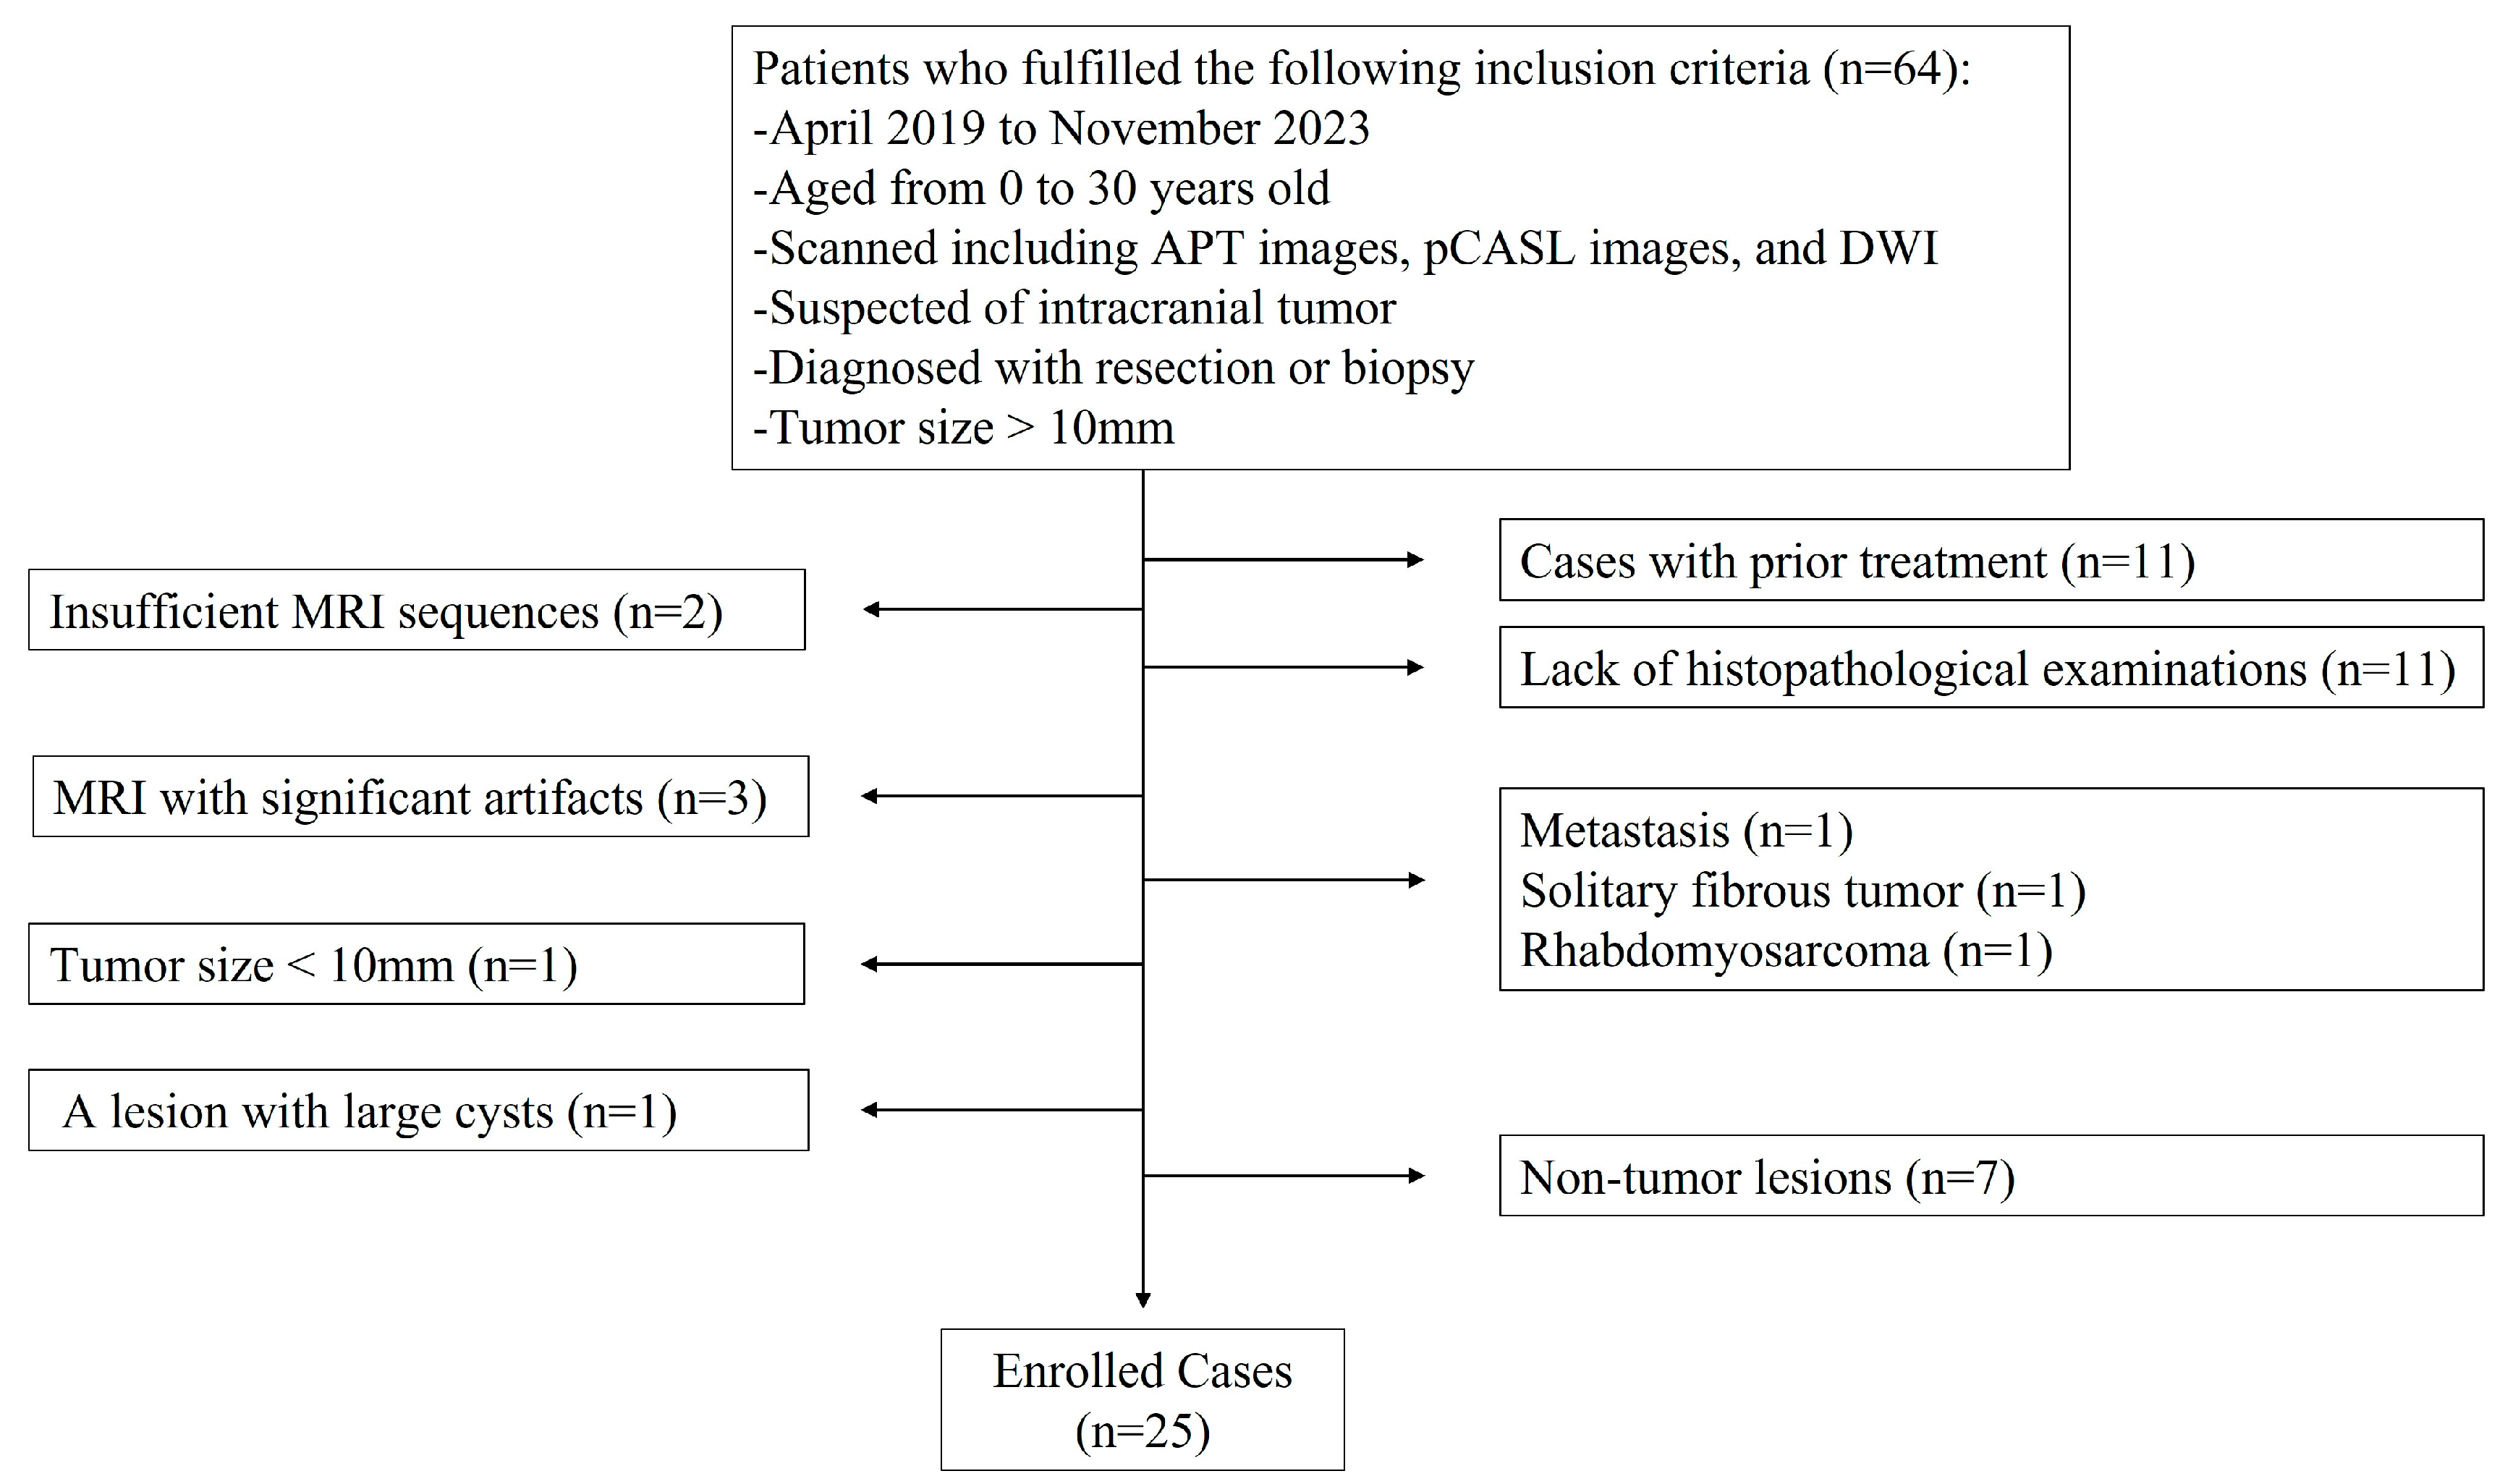

2.1. Subjects

3.1. Patients